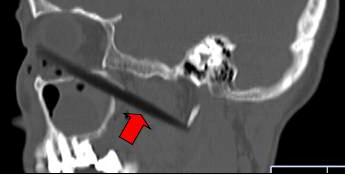

CT顯示筷子還插在腦部

取出的斷筷有9厘米

上周三,62歲的依姆林瓊(化名)在南平家中,有人在揮舞筷子時(shí),將筷子從她右眼眶插入,鼻孔瞬間出血。家人心急,用老虎鉗將筷子外端夾斷,剩下半截筷子嵌在頭面部,之后將其緊急送到福建醫(yī)科大學(xué)附一醫(yī)院。經(jīng)過(guò)1個(gè)多小時(shí)的緊急手術(shù),9厘米長(zhǎng)的斷筷被取出,由于筷子未插中眼球,患者眼睛未受影響。附一醫(yī)院耳鼻喉科副主任醫(yī)師張暉萍提醒,千萬(wàn)不可自行強(qiáng)拔已插入體內(nèi)的物體。傷者被送到附一醫(yī)院時(shí),醫(yī)生幾乎都看不到筷子了。在醫(yī)生的詢(xún)問(wèn)下,家屬這才說(shuō),當(dāng)時(shí),他們一心急,用老虎鉗將筷子外端夾斷。這下棘手了。若筷子是完整的還容易拔出,這下完全埋在眼眶下,可怎么取出?影像學(xué)檢查顯示,筷子就靠近視神經(jīng)管、頜內(nèi)血管分支,末端位于頸部大動(dòng)脈的前方。手術(shù)稍有不慎,就可能大出血。為了取出斷筷,附一醫(yī)院耳鼻喉科、頜面外科、眼科、影像科馬上聯(lián)合會(huì)診,擬定了三套手術(shù)方案。第一方案,從插入口直接拔;第二方案,從鼻腔取;第三方案,鋸開(kāi)眼眶取斷筷。最終,大家選擇了第一方案,因?yàn)閯?chuàng)傷最小,由耳鼻咽喉科張暉萍副主任醫(yī)師和眼科朱學(xué)軍主任醫(yī)師聯(lián)合急診手術(shù)。醫(yī)生們先從眼眶內(nèi)切開(kāi)傷口1厘米,才看到筷子斷端,順著原先插入口,在鼻窺鏡的幫助下,邊夾邊推,將筷子順利取出。取出的竹筷長(zhǎng)達(dá)9cm,周?chē)写罅磕撘?。?jīng)過(guò)多日抗感染治療,前日,老人才出院。